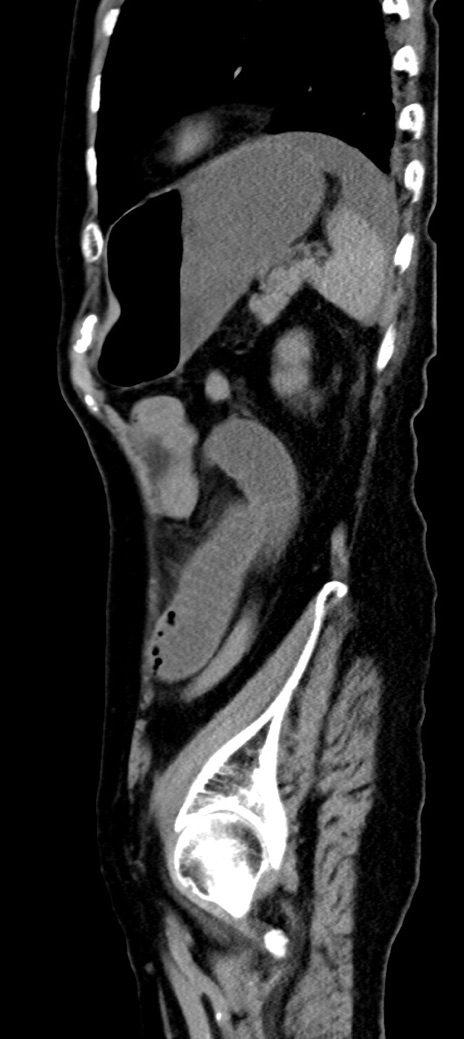

症例40(矢状断像)他院1日前

【症例】90歳代女性

【主訴】腹痛・嘔吐

【現病歴】 食欲低下、嘔吐があり昨日他院受診。肺炎と診断され入院となる。入院後より腹部全体に圧痛あり。胃管留置され経過みていたが、症状持続するため、

当院転院となる。

【既往歴】胸椎圧迫骨折、胆石症

【身体所見】腹部:中央に激痛あり、圧痛あり、反跳痛不明

【データ】WBC 17100、CRP 18.82